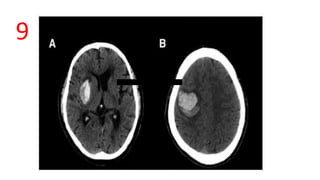

9

Blend sign

• Blend sign is composed of 2 parts with apparently different CT

attenuation

• A ,B - There is a well-defined margin between the hypo(active liquid

blood) and hyperattenuating (clots) regions.

• Predicts hematoma expansion

Blend sign • Blendsign is composed of 2 parts with apparently different CT attenuation • A ,B - There is a well-defined margin between the hypo(active liquid blood) and hyperattenuating (clots) regions. • Predicts hematoma expansion